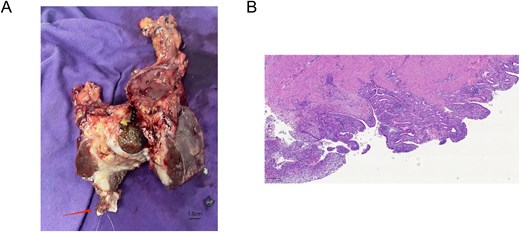

An open cholecystectomy was performed. Intraoperatively, the gallbladder was severely inflamed and densely adherent to the transverse colon. Adhesiolysis and partial colectomy with primary anastomosis were necessary. A cholecystectomy with a margin of liver tissue was performed adhering to the principle of R0 resection for suspected malignancy. Gross examination of the resected specimen clearly revealed thrombus formation within the middle hepatic vein (Fig. 2A). Intraoperative frozen section pathology confirmed chronic suppurative cholecystitis with no evidence of malignancy.

(A) Gross surgical specimen of the gallbladder and adjacent liver tissue, showing the site of thrombus formation in the middle hepatic vein (arrow). (B) Microscopic image showing chronic suppurative cholecystitis (Giemsa stain, ×50).

The patient’s postoperative course was complicated by fever, which resolved with antibiotic therapy. He was advanced to a normal diet and discharged on postoperative Day 19. Final pathology confirmed chronic suppurative cholecystitis and gallstones, with serosal inflammation of the resected colon and liver segments. The thrombus was organized and inflammatory in nature (Fig. 2B).